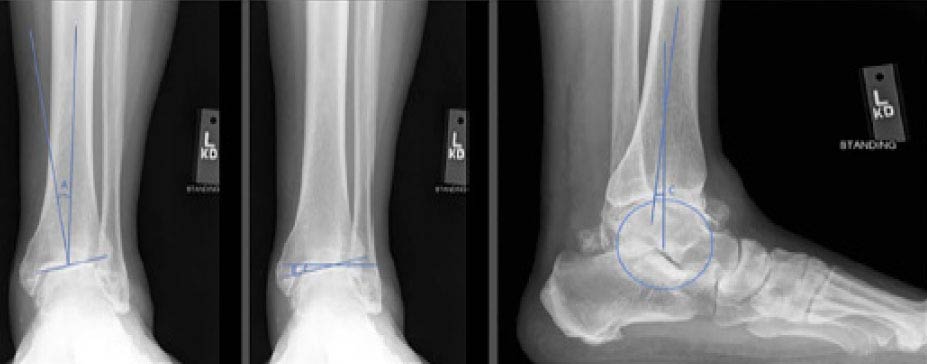

In this longer-term follow-up of a limited cohort (48 patients/50 ankles, average age at index surgery: 64 years), Salto Talaris fixed-bearing total ankle arthroplasty demonstrated good long-term survival (Kaplan-Meier estimated survivorship was 84.2%) with relatively low rates of revision or other complications. Patient-reported outcome and range of motion measures revealed good stability.

Source: Veale M, Endo A, Veale N, et al. Salto Talaris fixed-bearing total ankle arthroplasty: long-term results at a mean of 10.7 years. Foot Ankle Orthop. 2024;9(1):24730114231225458. doi: 10.1177/24730114231225458.